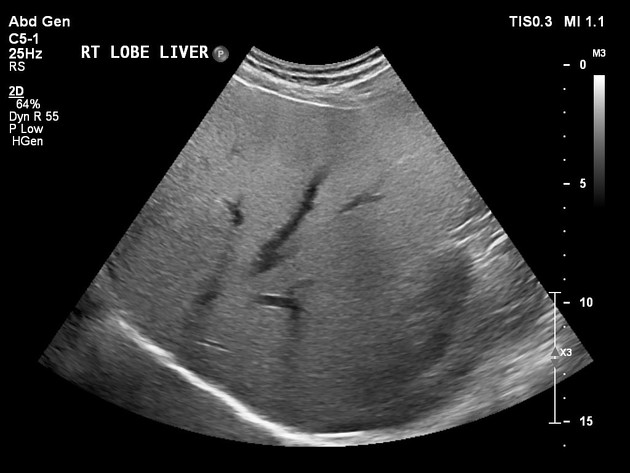

A alta da IRA realmente significa recuperação… ou apenas o começo da DRC futura? Albuminúria, reintrodução de IECA/BRA, iSGLT2 e seguimento precoce podem mudar completamente o prognóstico pós-IRA — e muita gente ainda foca só na creatinina da alta. Esse artigo do Clinical Kidney Journal traz 10 pontos práticos que todo nefrologista deveria revisar no seguimento pós-IRA.